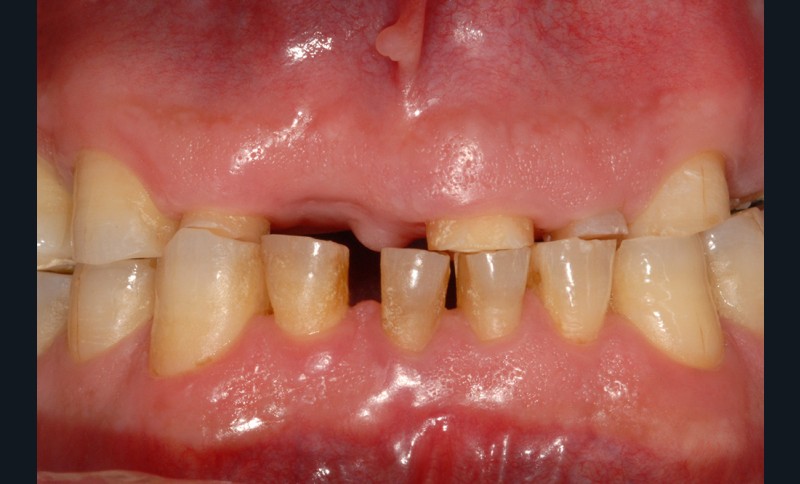

Elle correspond à la friction de deux corps solides en mouvement dont les surfaces sont en contact direct. Au niveau occlusal, lorsqu’elle prévaut sur les autres modes d’usure, l’attrition produit des surfaces planes, bien délimitées, à angles aigus, et parfois brillantes. Lorsque la dentine est exposée, elle se situe au même niveau que l’émail, sans aucune marge. Qu’elles soient localisées sur des tissus dentaires, des matériaux restaurateurs ou les deux simultanément, les facettes d’usure de dents antagonistes se correspondent en occlusion d’intercuspidie maximale (OIM) ou lors de faibles mouvements mandibulaires (fig. 1). Ces traces spécifiques, qui peuvent être locales ou globales, sont fondamentales pour mettre en évidence ce mode d’usure. L’origine de l’attrition est multifactorielle. Elle peut être liée aux contacts dento-dentaires furtifs et inconstants qui s’établissent lors de la déglutition et de la mastication, à des conditions occlusales particulières (édentation non compensée, malposition, malocclusion), à certaines parafonctions de l’éveil et, surtout, à un bruxisme du sommeil (fig. 2).